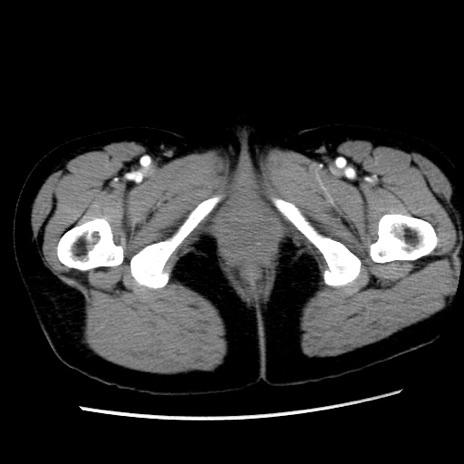

症例10(横断像)

【症例】 50歳代女性

【主訴】 腹痛

【現病歴】前日生レバーを食べた。今朝に排便あり。 昼前に突然発症の腹痛を生じ、当院救急外来を受診した。

【既往歴】 子宮筋腫にてで子宮全摘後

【身体所見】 意識清明、腹部:平坦、軟、下腹部やや左を中心に圧痛・反跳痛あり、筋性防御あり

【データ】WBC 7800、CRP 0.07